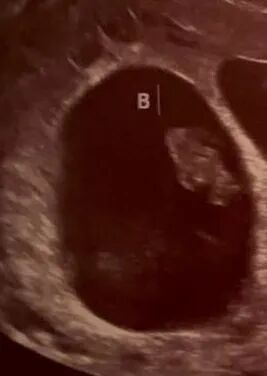

爱妈M通过双胚胎移植成功怀孕,带来了双倍的喜悦。双胚胎移植可以显着提高怀孕率,然而这种方法也存在风险,如增加多胎妊娠相关的并发症,包括早产和妊娠高血压等,同时也可能对子宫和胎儿健康带来额外负担。但选择这种方法前,建议准父母提前进行详细咨询。我们最近已经迎来了好几对健康的双胞胎,这些成功案例让我们充满信心,相信好运将会持续!

我们最近已经迎来了好几对健康的双胞胎,这些成功案例让我们充满信心,相信好运将会持续!我们的准父母之前已经成功地迎来了一个宝贝,如今他们希望好事成双,一次抱回两个宝宝,组建一个更加热闹的大家庭。